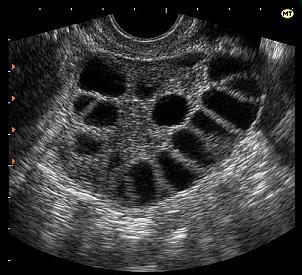

Приехали... тенденция к поликистозным яичникам

На сегодняшнем узи вот что!

Есть те, кому поставили в заключении узи тенденцию к поликистозности яичников?